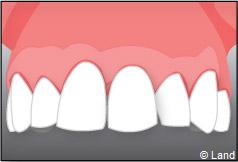

Situation clinique initiale

Situation clinique terminée